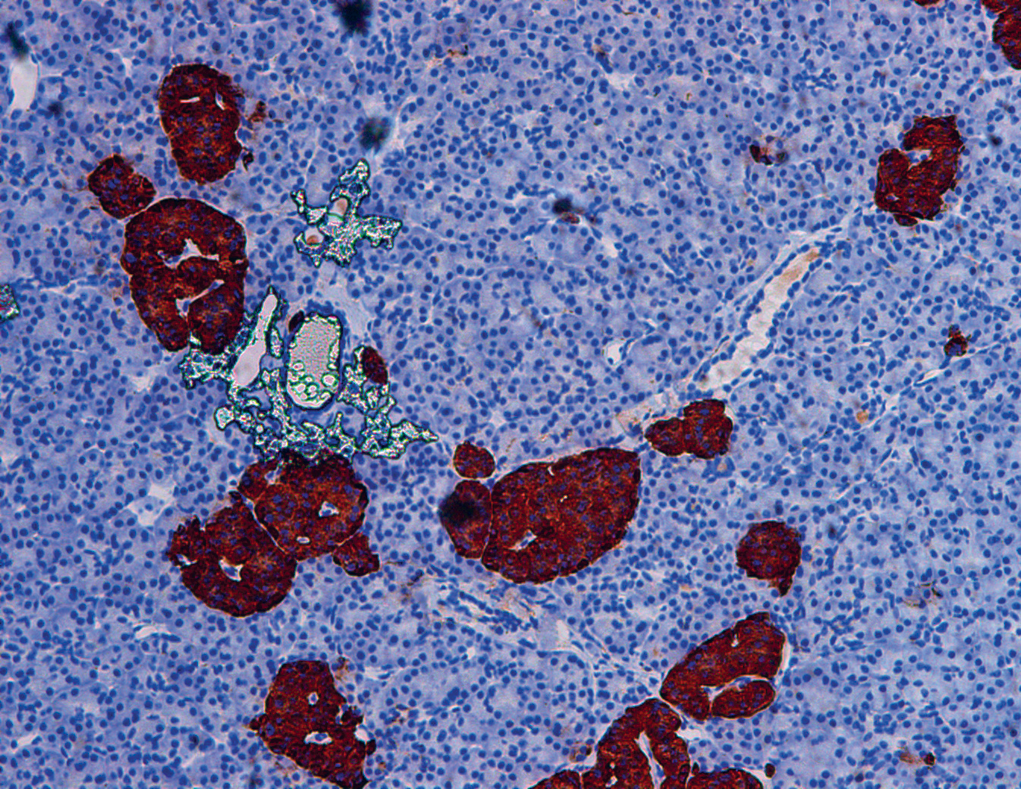

Pancreatic cells called “islets of Langerhans”

If I have to cite one example, it is the transplantation of pancreatic cells called “islets of Langerhans” into patients with severe type 1 diabetes (work carried out by the Translational Research in Diabetes unit). This procedure is now reimbursed up to 100% by the French Assurance Maladie.